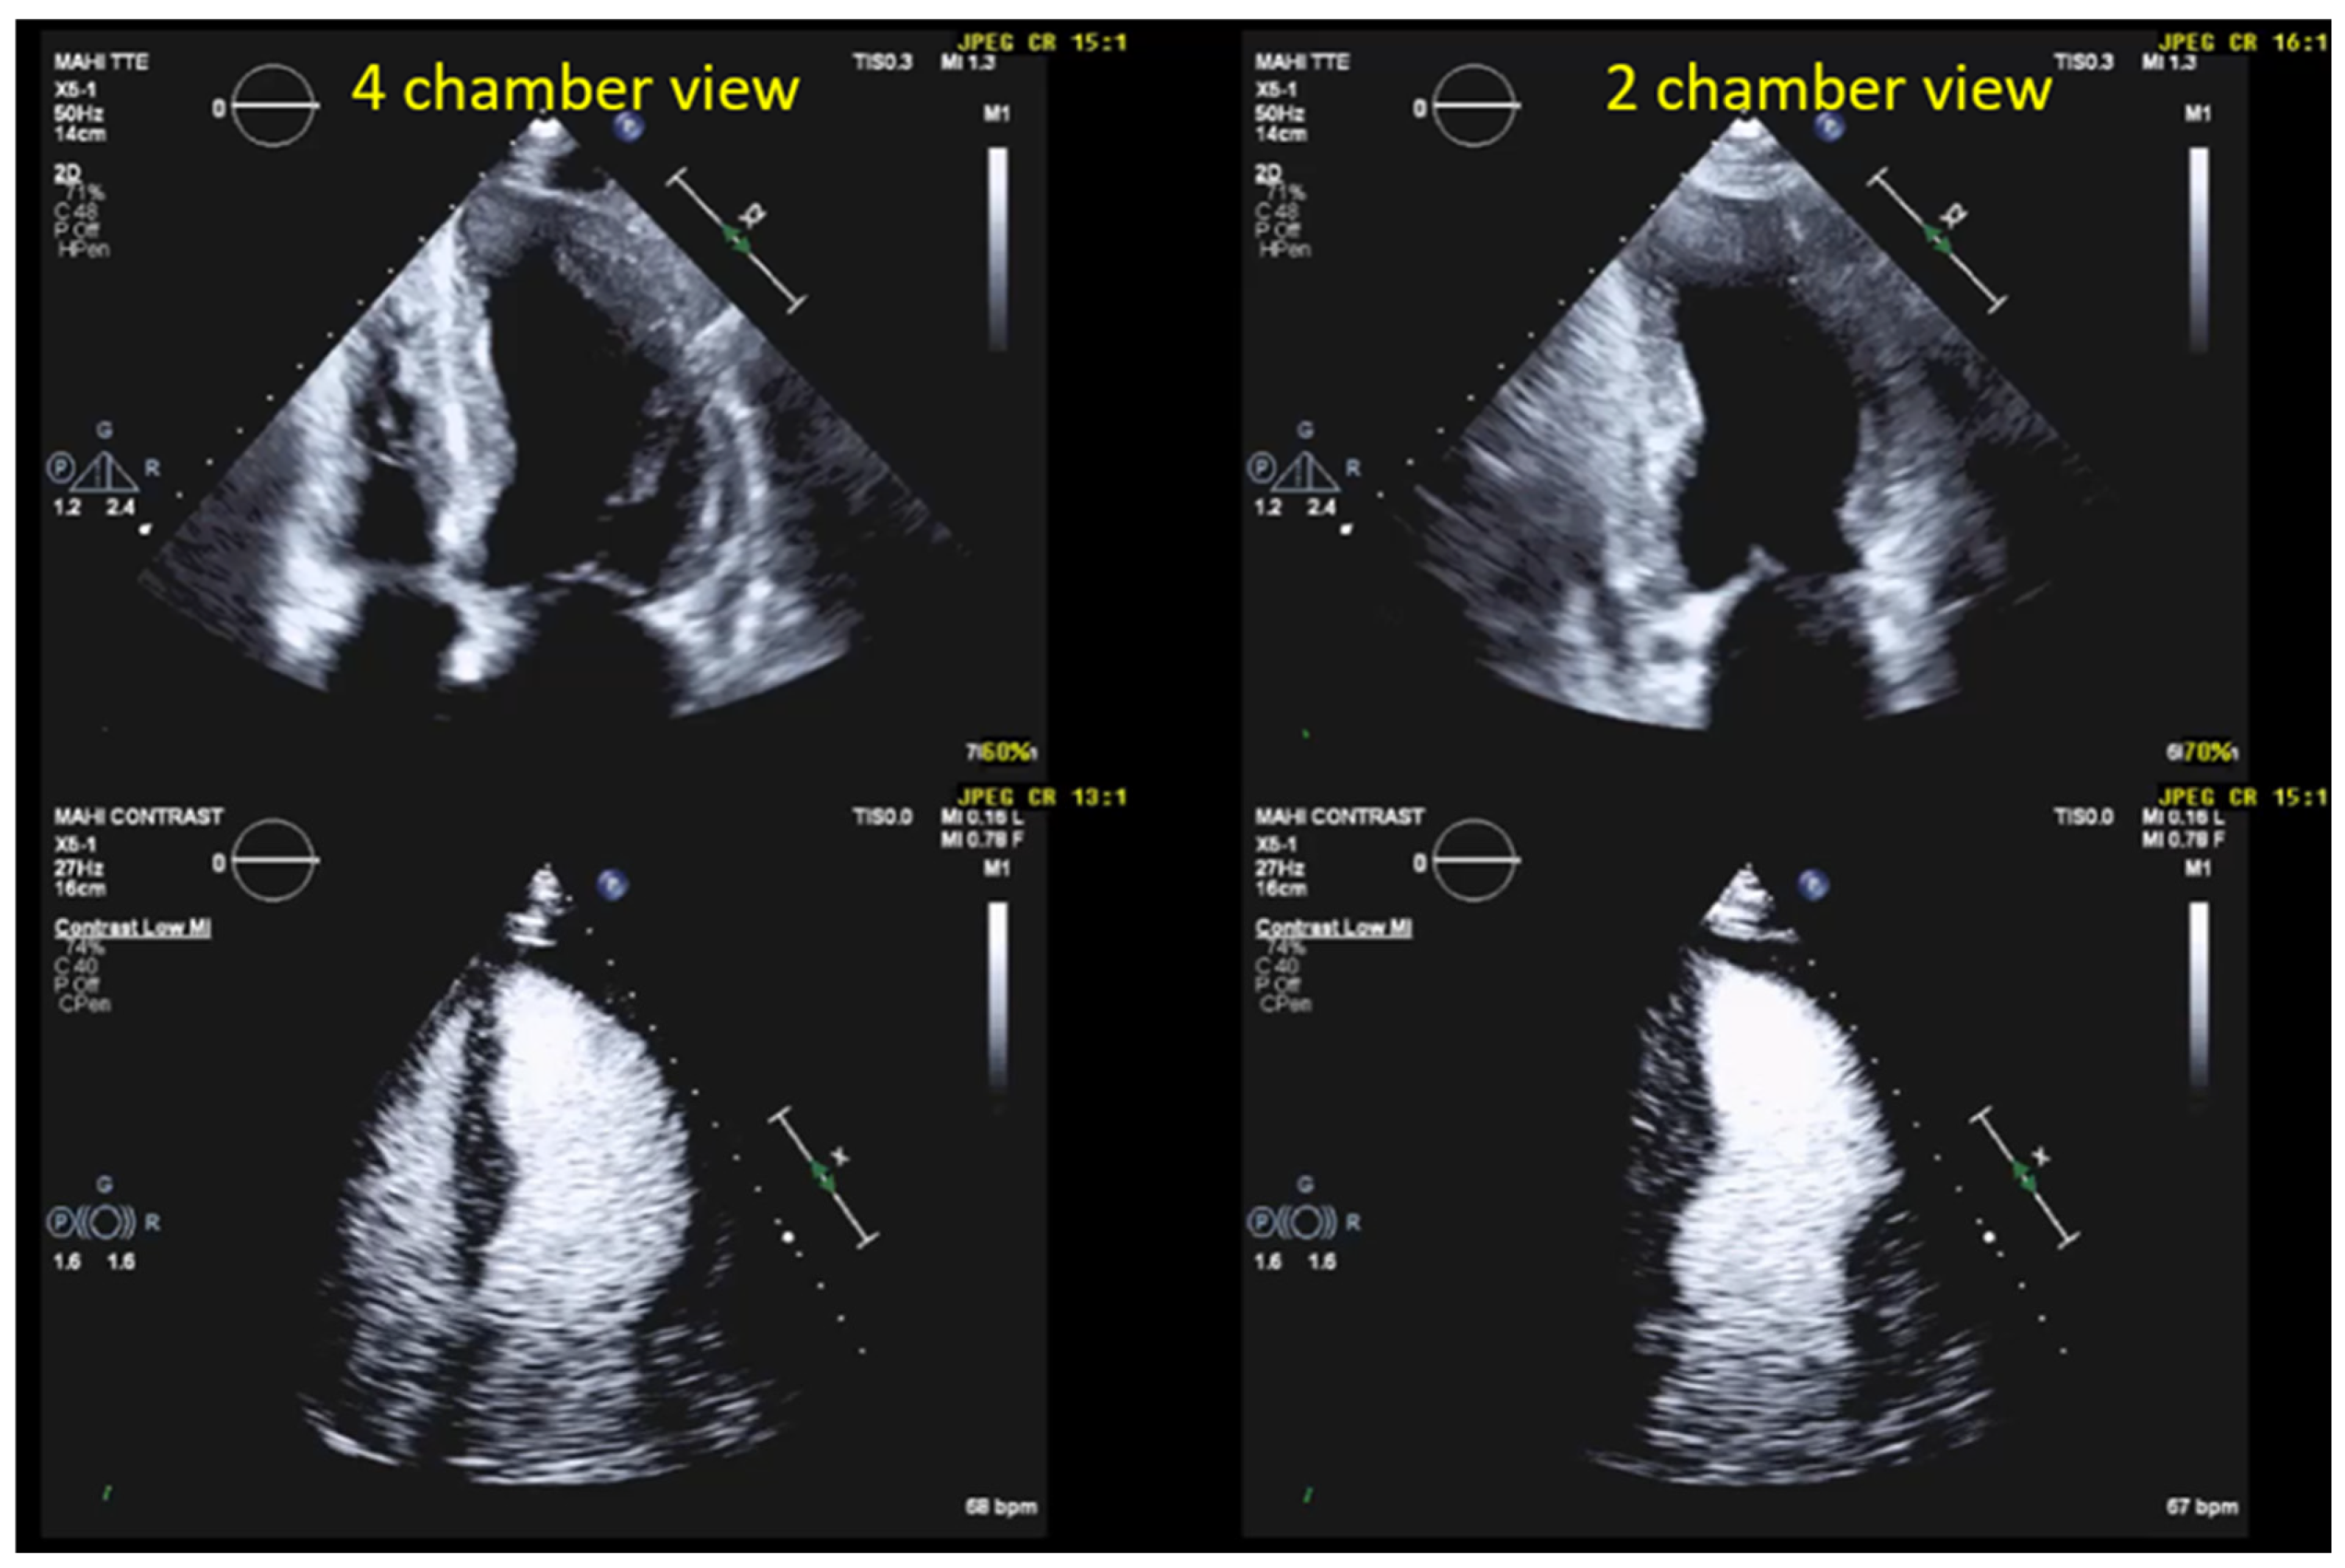

4.2.1. Technical Aspects and Settings

4.2.2. Pre-Assessment and Primary Scan Plane

4.2.3. CEUS Procedure

4.3. Optimization of LV Opacification